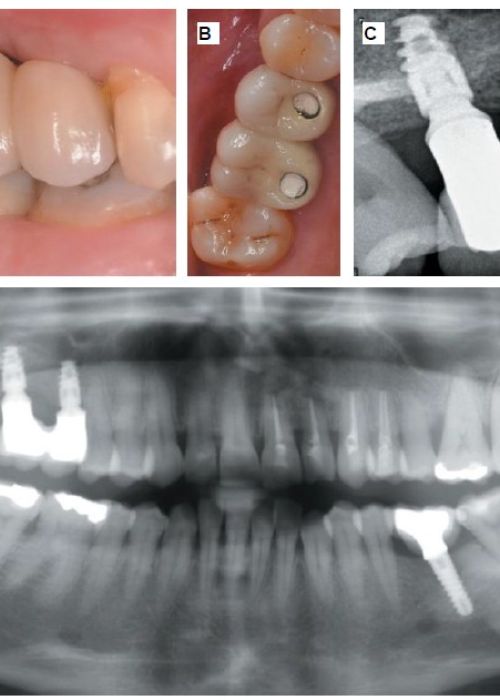

Clinical, radiographic and histomorphometric behaviour of the autologous tooth as a biomaterial in lateral access maxillary sinus elevation. Case report with six months of post-prosthetic loading follow-up

Comportamiento clínico, radiográfico e histomorfométrico del diente autólogo como biomaterial en elevación de seno maxilar de acceso lateral. Caso clínico con seis meses de seguimiento post-carga protésica